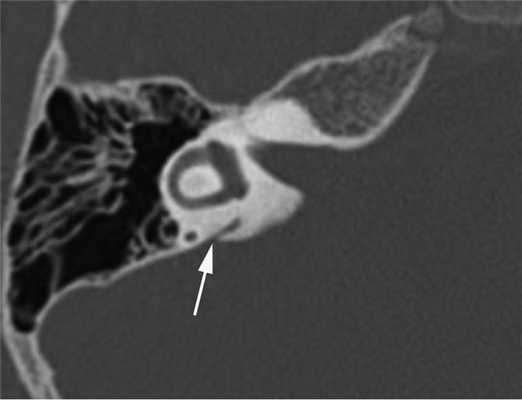

Прижизненная визуализация водопровода преддверия стала возможной с внедрением в клиническую практику компьютерной томографии (КТ). На томограммах неизмененный водопровод преддверия (рис. 1) визуализируется в виде узкой линейной щели шириной до 1,5 мм, идущей от преддверия к задней грани пирамиды и заканчивающийся на ней отверстием, расположенным кзади от внутреннего слухового прохода [3, 4].

Рис. 1. Неизмененный водопровод преддверия (стрелка). Компьютерная томограмма правой височной кости в аксиальной проекции.